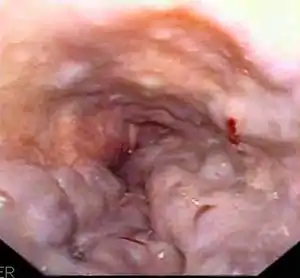

Esophageal varices are extremely dilated sub-mucosal veins in the lower third of the esophagus.[1] They are most often a consequence of portal hypertension,[2] commonly due to cirrhosis.[3] People with esophageal varices have a strong tendency to develop severe bleeding which left untreated can be fatal. Esophageal varices are typically diagnosed through an esophagogastroduodenoscopy.[4]

![]() | |

| Gastroscopy image of esophageal varices with prominent cherry-red spots | |

Dilated submucosal veins are the most prominent histologic feature of esophageal varices. The expansion of the submucosa leads to elevation of the mucosa above the surrounding tissue, which is apparent during endoscopy and is a key diagnostic feature. Evidence of recent variceal hemorrhage includes necrosis and ulceration of the mucosa. Evidence of past variceal hemorrhage includes inflammation and venous thrombosis.